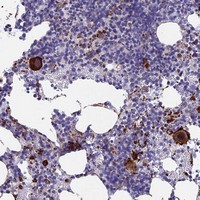

- Immunohistochemical staining of human bone marrow with C15orf59 polyclonal antibody (Cat # PAB23826) shows strong cytoplasmic positivity in megakaryocytes at 1:500-1:1000 dilution.

- Immunohistochemistry (Formalin/PFA-fixed paraffin-embedded sections)